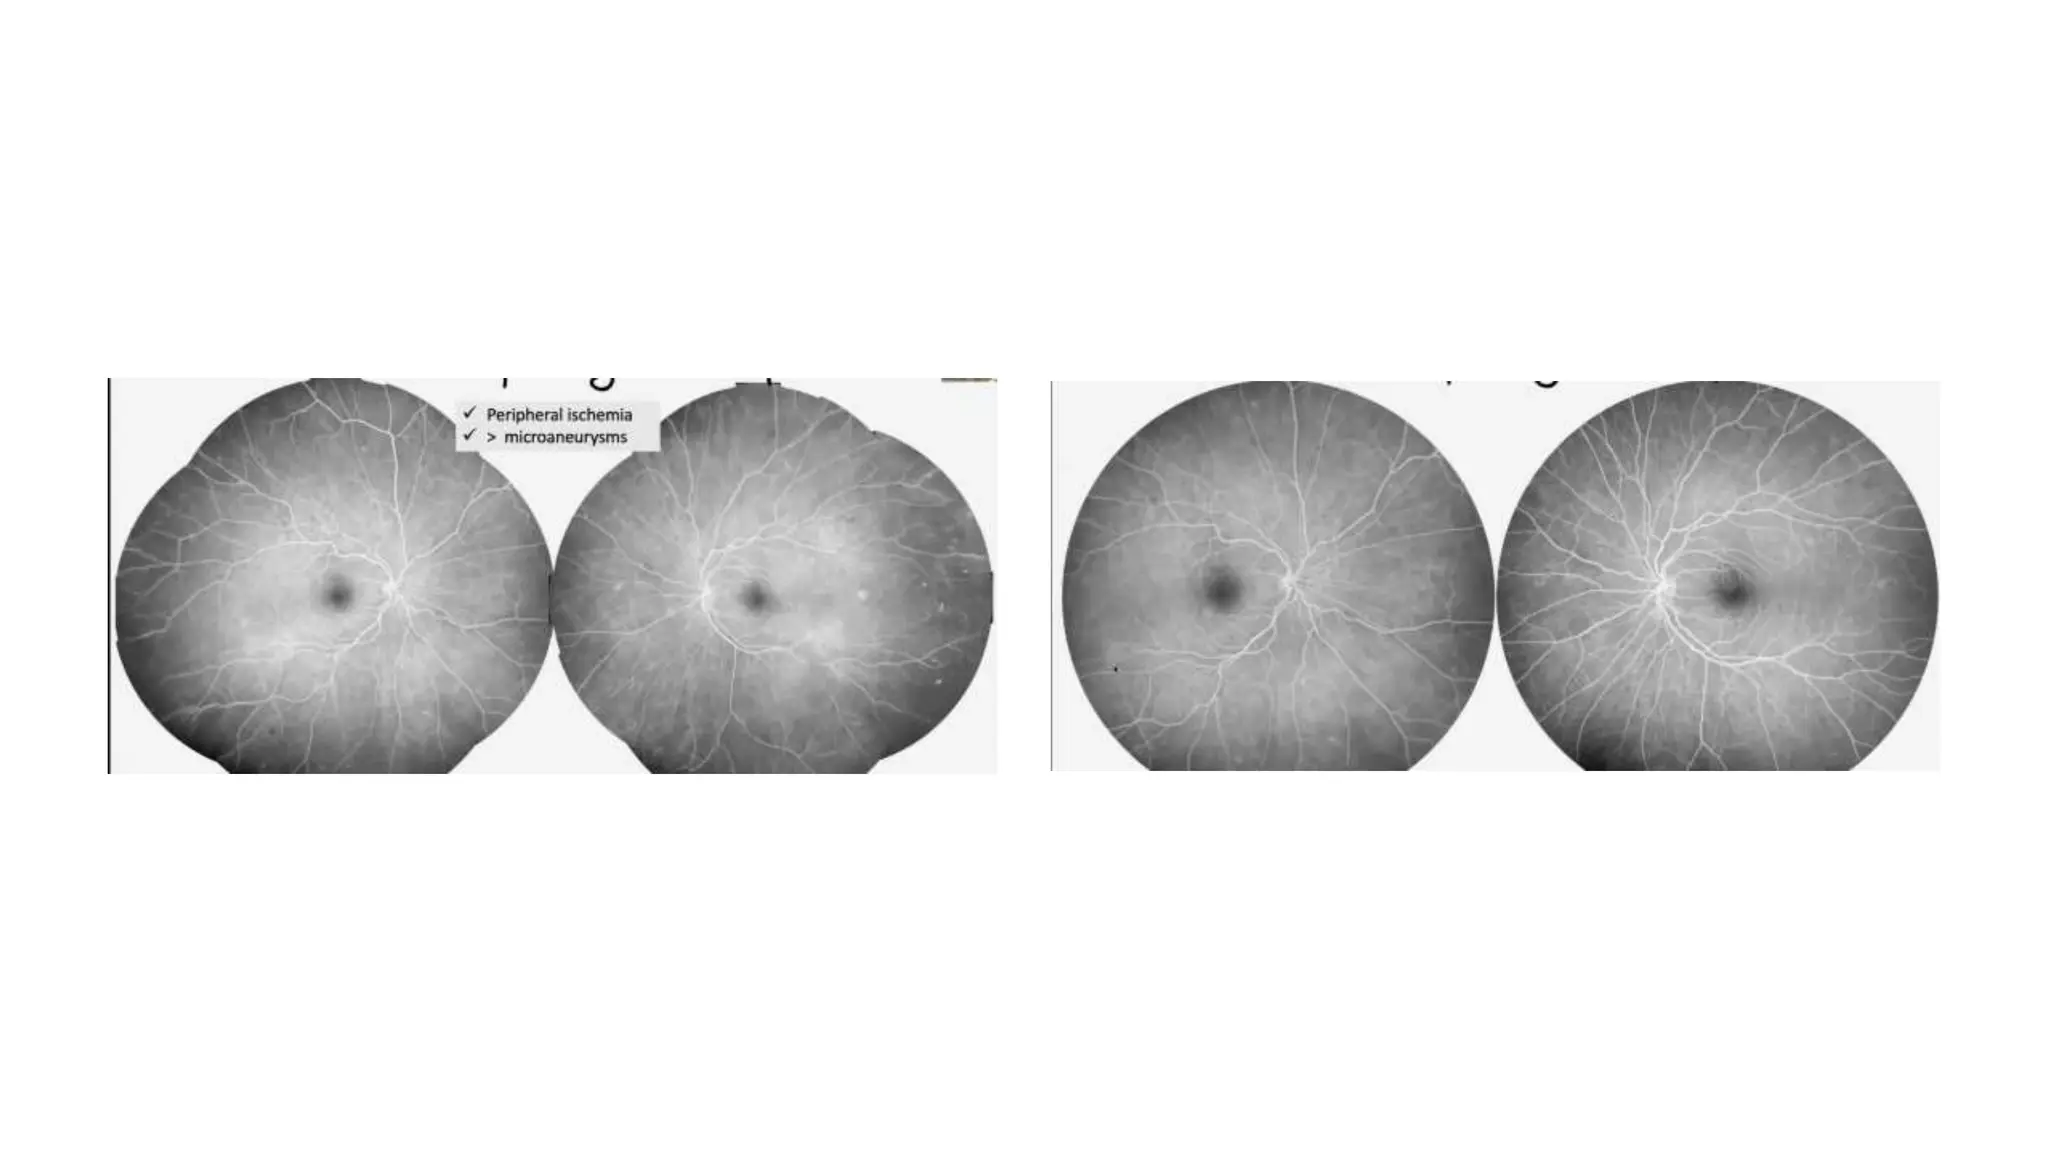

Ultra-Wide Field Imaging

ü Images of up to 200º of the retina (80%).

ü Screening

• May not require mydriasis

• 133º-200º with 1 single image (vs. 30º-50º standard cameras).

ü UWF imaging vs 7 ETDRS fields

à15% greater DR stage

ü Predominantly peripheral lesions

• >50% of lesions outside 7 ETDRS fields

• X 3.2 progression of 2 steps DR

• X 4.7 progression into PROLIFERATIVE DR

• #9 Wide field

• #10 Mild nonproliferative BCVA 20/20